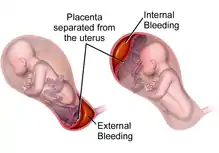

| |

| Drawing of internal and external bleeding from placental abruption | |

Placental abruption is when the placenta separates early from the uterus, in other words separates before childbirth.[2] It occurs most commonly around 25 weeks of pregnancy.[2] Symptoms may include vaginal bleeding, lower abdominal pain, and dangerously low blood pressure.[1] Complications for the mother can include disseminated intravascular coagulopathy and kidney failure.[2] Complications for the baby can include fetal distress, low birthweight, preterm delivery, and stillbirth.[2][3]

A placental abruption caused by arterial bleeding at the center of the placenta leads to sudden development of severe symptoms and life-threatening conditions including fetal heart rate abnormalities, severe maternal hemorrhage, and disseminated intravascular coagulation (DIC). Those abruptions caused by venous bleeding at the periphery of the placenta develop more slowly and cause small amounts of bleeding, intrauterine growth restriction, and oligohydramnios (low levels of amniotic fluid).[9]

In the vast majority of cases, placental abruption is caused by the maternal vessels tearing away from the decidua basalis, not the fetal vessels. The underlying cause is often unknown. A small number of abruptions are caused by trauma that stretches the uterus. Because the placenta is less elastic than the uterus, it tears away when the uterine tissue stretches suddenly. When anatomical risk factors are present, the placenta does not attach in a place that provides adequate support, and it may not develop appropriately or be separated as it grows. Cocaine use during the third trimester has a 10% chance of causing abruption. Though the exact mechanism is not known, cocaine and tobacco cause systemic vasoconstriction, which can severely restrict the placental blood supply (hypoperfusion and ischemia), or otherwise disrupt the vasculature of the placenta, causing tissue necrosis, bleeding, and therefore abruption.[9]

In most cases, placental disease and abnormalities of the spiral arteries develop throughout the pregnancy and lead to necrosis, inflammation, vascular problems, and ultimately, abruption. Because of this, most abruptions are caused by bleeding from the arterial supply, not the venous supply. Production of thrombin via massive bleeding causes the uterus to contract and leads to DIC.[9]

The accumulating blood pushes between the layers of the decidua, pushing the uterine wall and placenta apart. When the placenta is separated, it is unable to exchange waste, nutrients, and oxygen, a necessary function for the fetus's survival. The fetus dies when it no longer receives enough oxygen and nutrients to survive.[9]